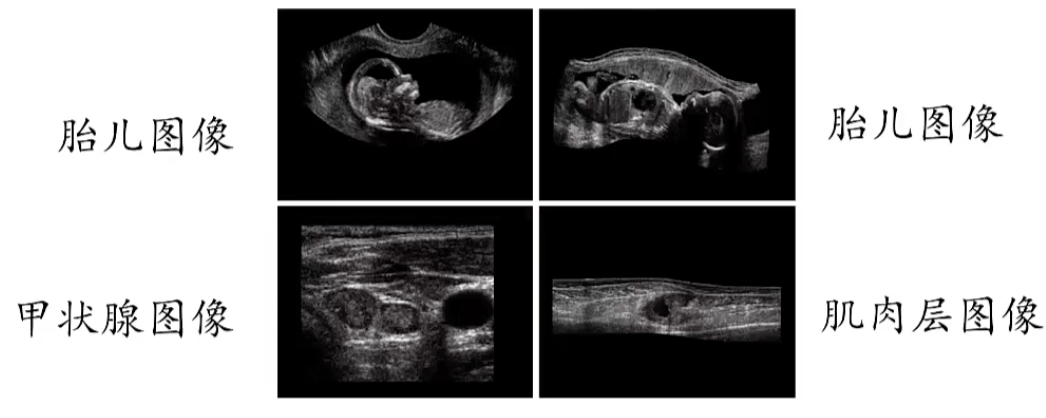

声波成像主要用于地质勘探、工业以及医学领域,在地质勘探中主要使用低频率的声波,也就是频率为几百赫兹的声波。在医学领域中主要使用超声波,即百万赫兹以上的声波。

| 在医学领域中通过探头发射和接收几百万赫兹的声波,并且探头可以沿着病人身体表面移动从而形成一定的角度以获得不同的视图 | ![]() |